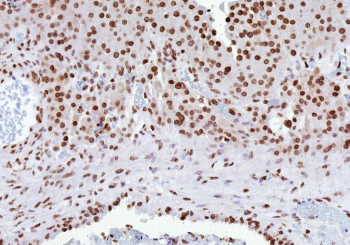

Immunohistochemistry analysis of Estrogen receptor beta in human ovarian carcinoma tissue. Formalin-fixed, paraffin-embedded human ovarian carcinoma tissue was stained using Estrogen receptor beta/ER beta antibody (clone ESR2/9709), showing nuclear immunoreactivity in tumor cells consistent with Estrogen receptor beta expression encoded by the ESR2 gene. Heat-induced epitope retrieval was performed by heating tissue sections in 10 mM Tris with 1 mM EDTA, pH 9.0, at 95oC for 45 minutes, followed by cooling at room temperature for 20 minutes prior to immunostaining.